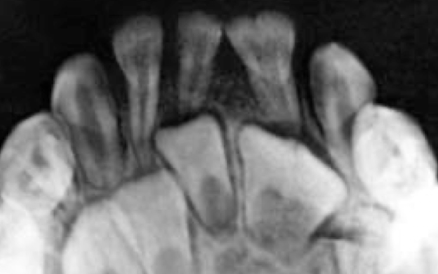

What dental anomaly is seen here?

concrescence

What dental anomaly is seen in these teeth?